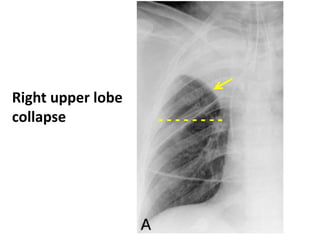

Right upper lobe collapse

Right upper lobe collapse .

Segmental or lobar density

Compensatory hyperinflation of

normal lung

- - - - - - - -

Right upper lobe

collapse